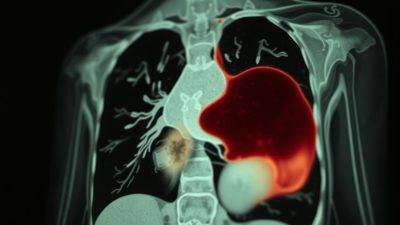

Imaging: Rontgen dan CT Scan

Teknik imaging seperti rontgen dada dan CT scan sangat penting dalam mendiagnosis Hemothorax. Rontgen dada dapat menunjukkan adanya darah di rongga pleura, sedangkan CT scan memberikan gambaran yang lebih detail tentang kondisi paru-paru dan struktur sekitarnya.

Penggunaan teknik imaging ini memungkinkan dokter untuk menentukan tingkat keparahan Hemothorax dan merencanakan penanganan yang sesuai.